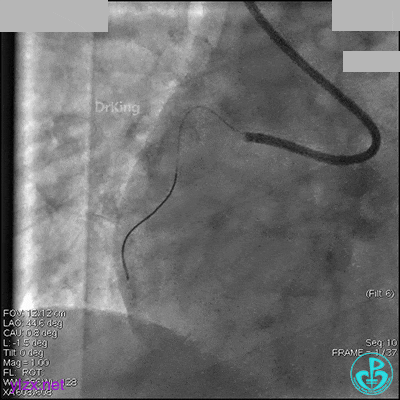

AL 1.0指引导管到位,简单短时尝试导丝不能顺利通过前降支或回旋支病变。改变策略处理右冠脉病变,计划植入2枚支架。AL指引导管到位,Sion blue导丝到达右冠脉远端。导丝通过后1.5mm及2.5mm球囊14~16atm充分扩张中段病变。

右冠脉中段充分扩张后欲植入3.5×38mm支架时,支架难以通过中远段扭曲处,且指引导管、导丝弹出飞扬。反复尝试导丝重新到达右冠脉远端时通过不顺利,局部造影剂滞留,远端血流接近3级。